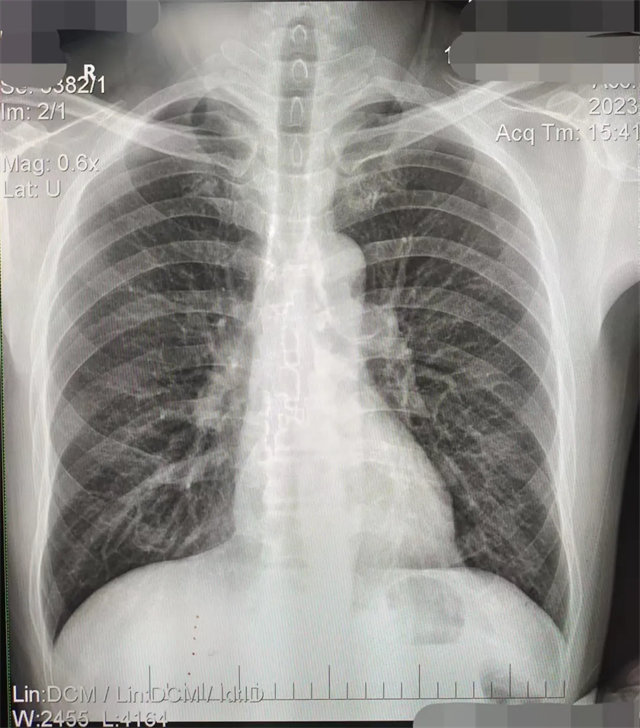

缺陷:肩胛骨未完全拉離肺野,吸氣不完全,存在金屬偽影遮擋,略有聳肩,且肺尖顯示不好,圖像顆粒感較強(qiáng),管電流量不夠,信噪比偏低。

解決:去除金屬物品后,按標(biāo)準(zhǔn)體位,使患者雙肩旋前與前胸一并緊貼成像件,適當(dāng)調(diào)高mAs,然后深吸氣后屏氣曝光。